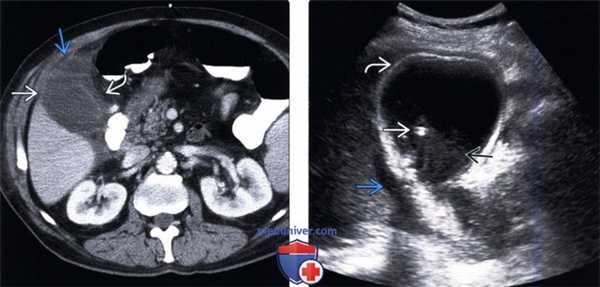

(Левый) На поперечном УЗ срезе определяется сладж, заполняющий желчный пузырь. Сладж имеет такую же эхогенность, как и печень, это состояние называют «гепатизацией».

(Правый) Положение пациента на левом боку. На продольном УЗ срезе визуализируется смещающийся книзу под действием гравитации сладж, напоминающий полип. Стенка желчного пузыря не изменена.